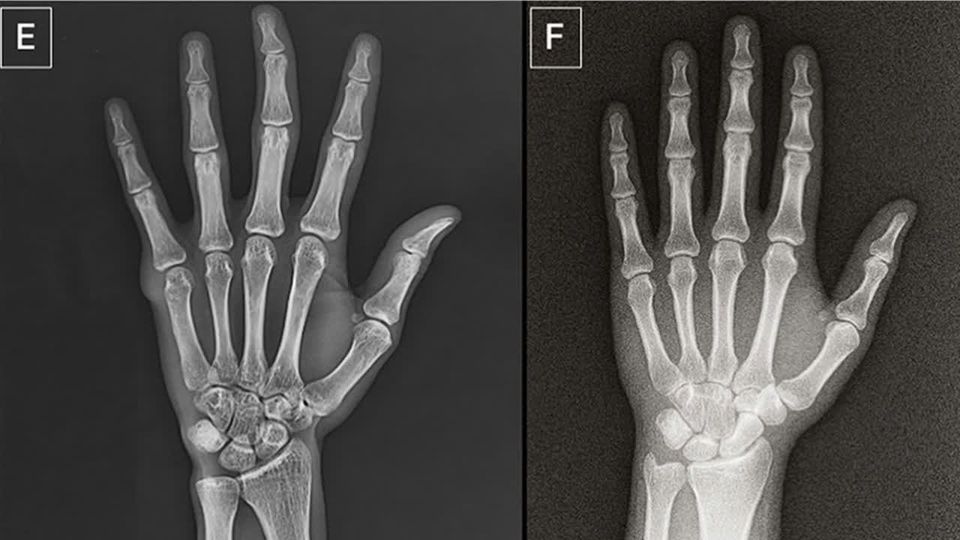

Welches Röntgen-Bild ist ein Deep-Fake?

Künstliche Intelligenz wird immer besser – und damit auch immer gefährlicher. Jetzt kann KI sogar täuschend echte Röntgenbilder erzeugen. Welches ist das Original und welches die Fälschung?